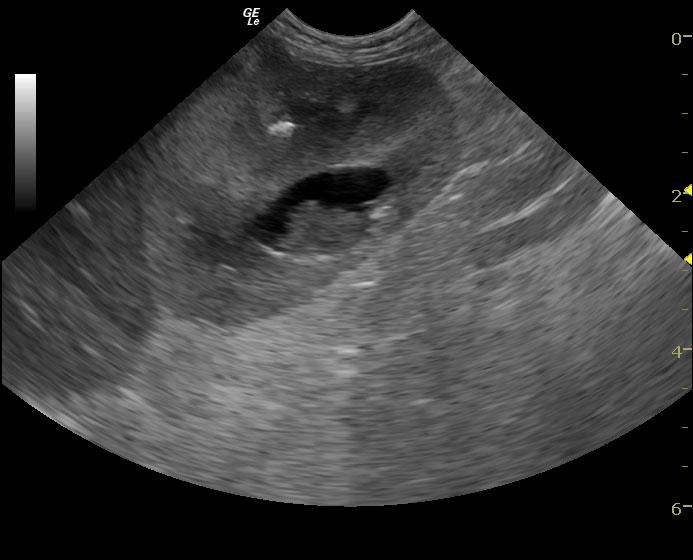

An 11-year-old SF Bichon dog was presented with a history of 3-4 days of lethargy, anorexia, and vomiting. Abnormalities on physical examination were tense abdomen, mild dehydration, and moderate dental tartar. Urinalysis (free-flow sample) showed inappropriate SG, (1.017), hematuria, and, pyuria. Abnormalities on CBC and serum biochemistry were leukocytosis, monocytosis, neutrophilia, azotemia, and hyponatremia.